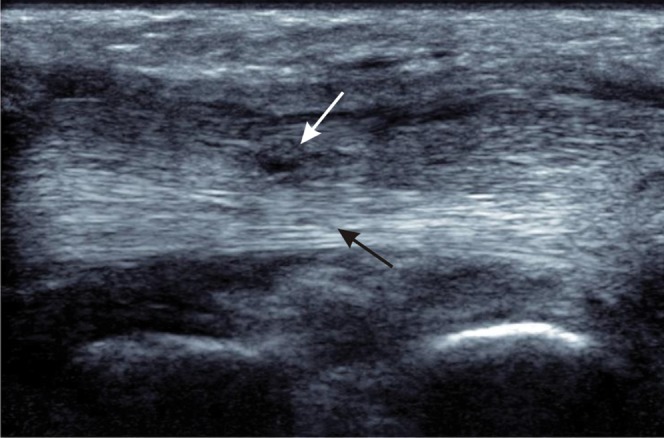

Imagen ecográfica de una rotura parcial del tendón tibial posterior

A continuación, te presento un corte ecográfico longitudinal en el que se ve una rotura parcial del tendón.

La parte profunda del tendón (flecha negra) conserva el patrón fibrilar normal y brillante propias de un tendón sano. Son las fibras que aún resisten y mantienen la integridad estructural.

Sin embargo, en la zona superficial (flecha blanca) vemos una imagen completamente diferente. Se observa un adelgazamiento localizado y una pérdida total del patrón ecogénico habitual. Esa área oscura y desorganizada representa el defecto focal donde las fibras se han seccionado. El patrón fibrilar no es continuo.